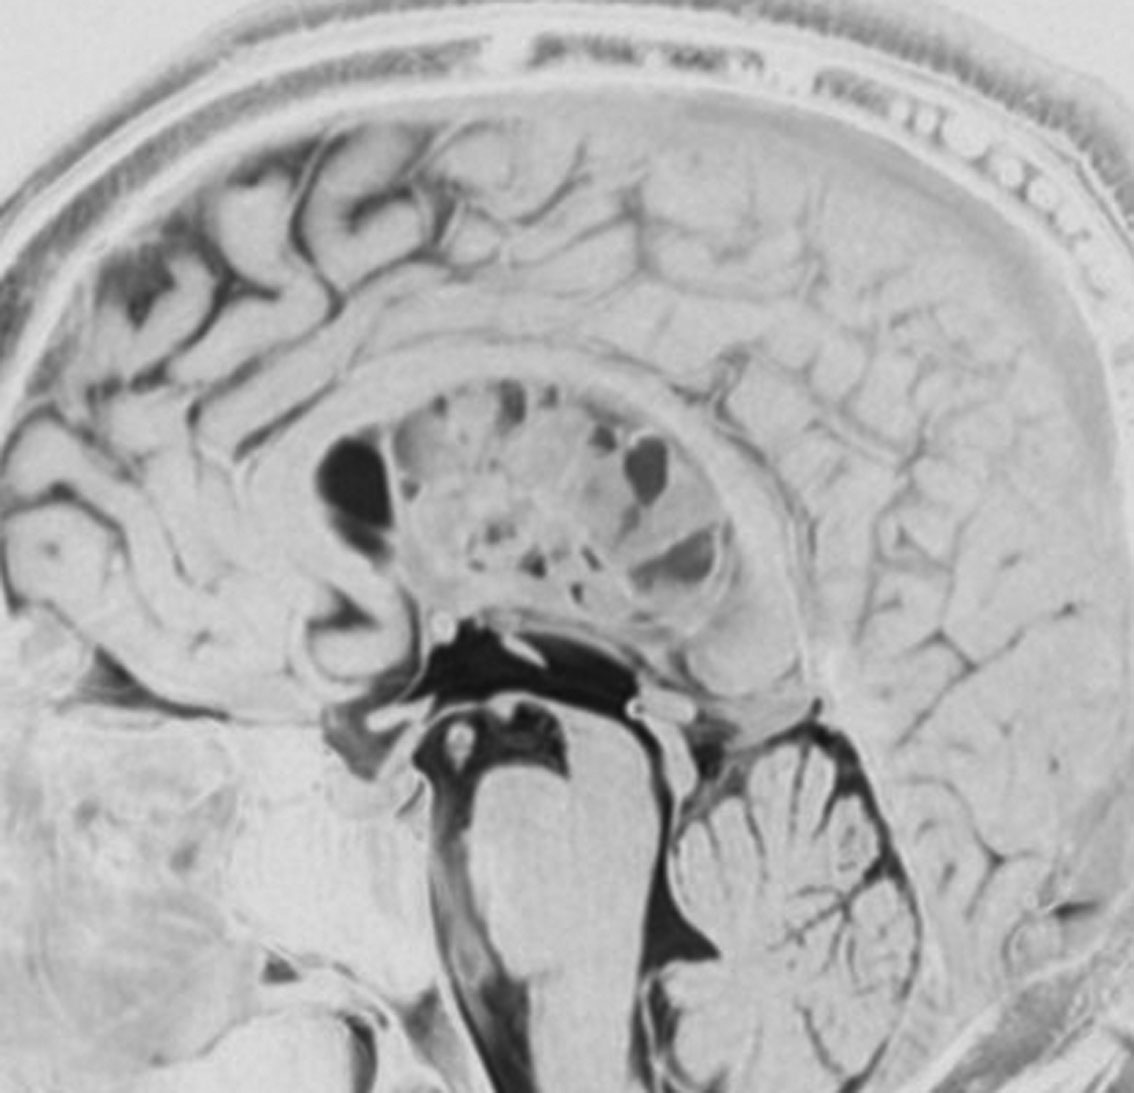

巨大な上衣下腫,でも良性のもの

52歳の男性で,2008年に脳ドックで見つかって無症状でした。中枢性神経細胞種 central neurocytomaを疑いましたが,上衣下腫 subependymomaはまったく考慮に入れませんでした。壮年男性でしたから経過観察しました。右側は2019年,11年後のものです。徐々に増大して水頭症になり歩行障害がでてきました。

手術前の画像です。血管が豊富で大きな導出静脈がみられ,腫瘍内出血もあります。ガドリニウムでは部分的に増強されます。CISS/FIESTAの画像では,透明中核から発生したようにみえて,脳浸潤は全くありません。脳弓は腫瘍の底面にありますが,もちろん境界はっきりしません。これらもcentral neurocytomaの画像所見として捉えられるものです。

transcallosal approach 経脳梁法で亜然摘出しました。底面には脳弓があって剥離できないから全摘出はできません。病理所見は,のう胞形成を伴う線維性基質の中に楕円形の細胞が索状または小巣状に増生するものでsubependymomaと診断されました。異型は軽度で,核分裂像はなく,MIB-1染色率は1%以下のWHO grade Iの所見。EMAは細胞質にdot likeに陽性でしたがわずかであり,ependymomaとの合併腫瘍の診断には至りませんでした。

術後1年の画像です。無症状で復職できています。